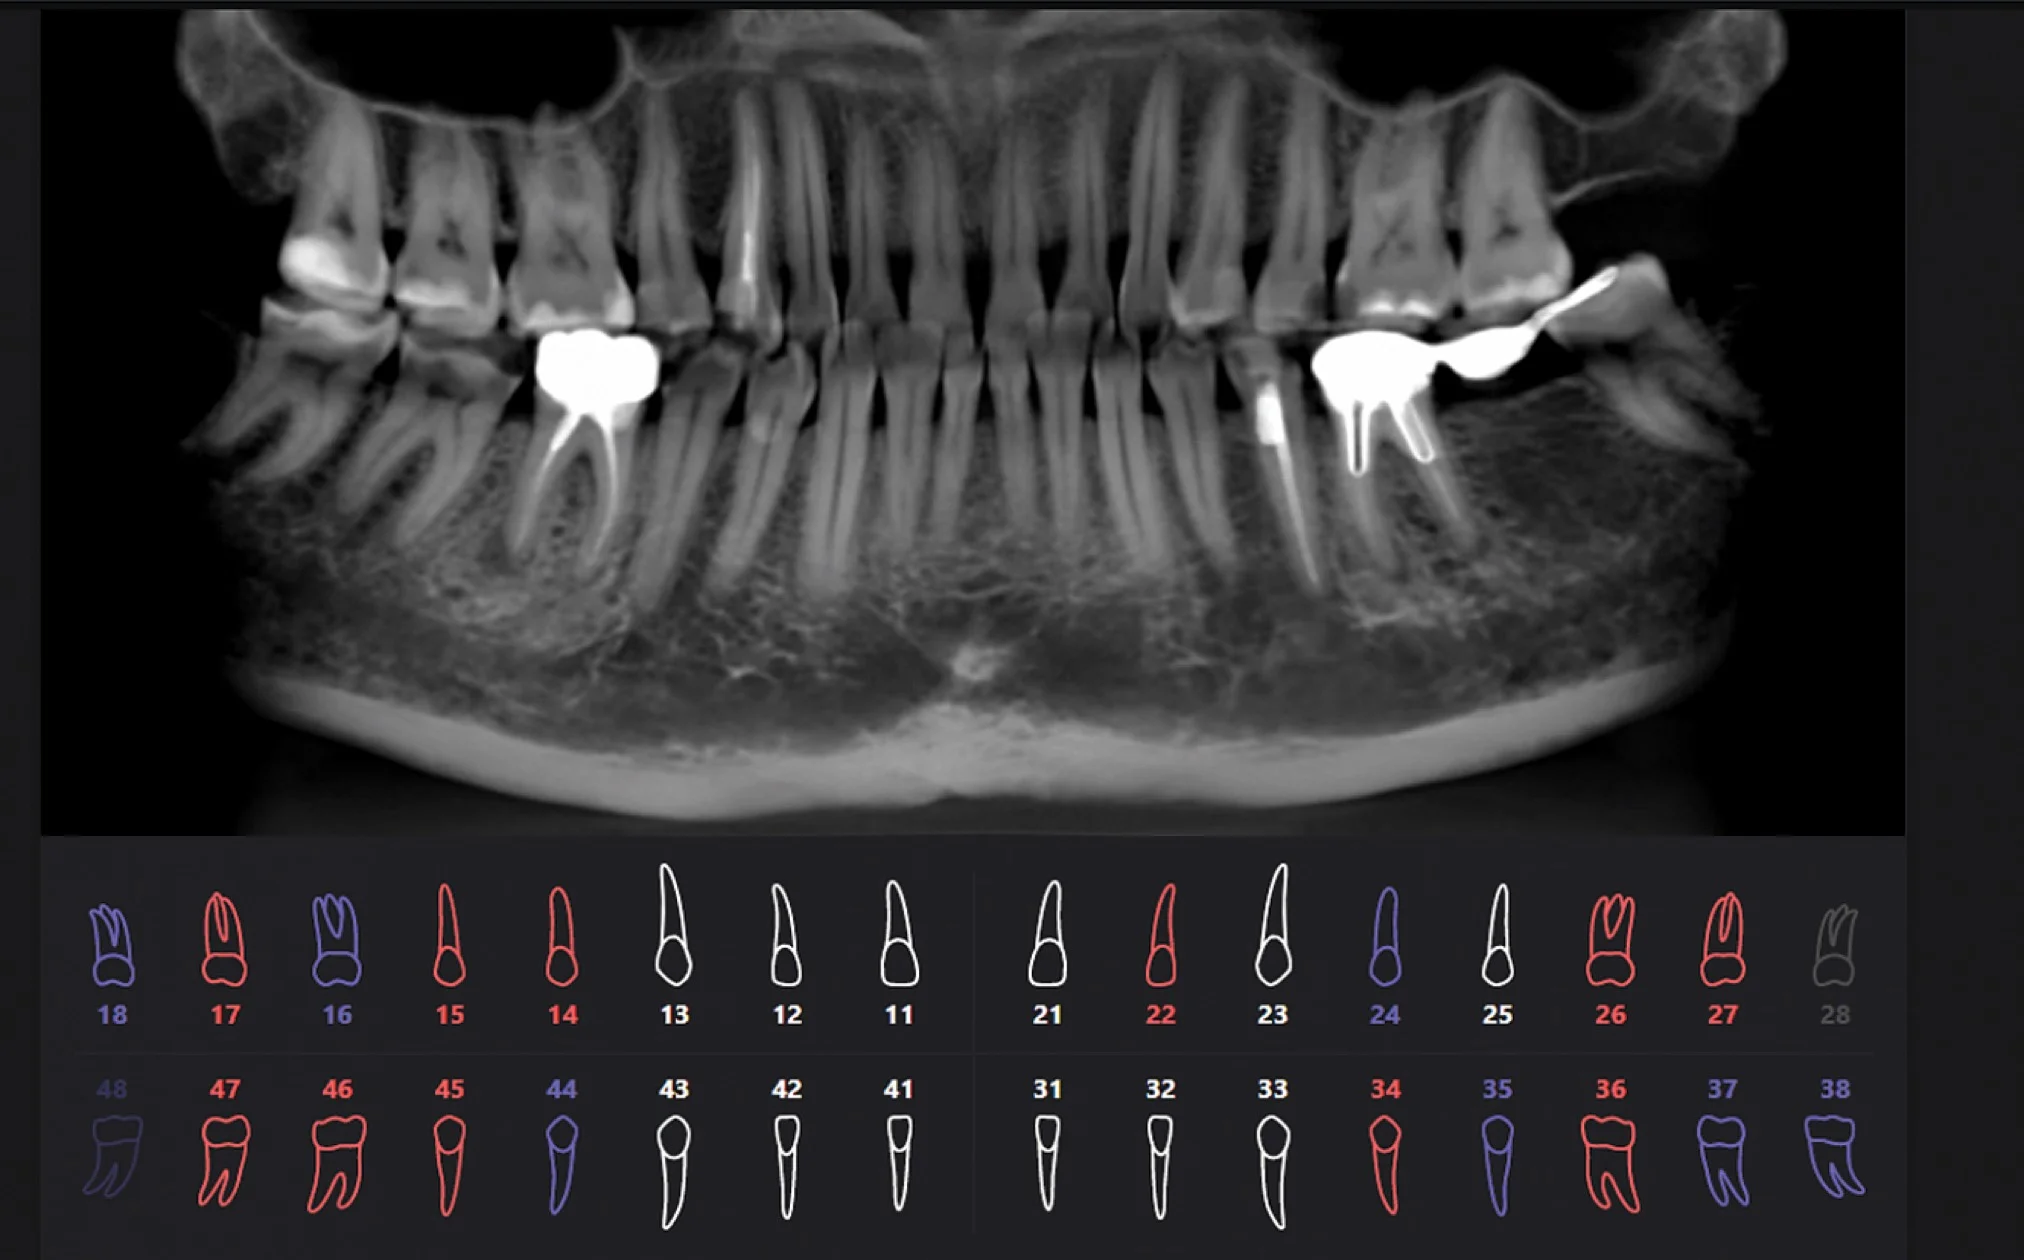

Результат работы искусственного интеллекта

Красным цветом показаны проблемные зубы, синим цветом — зубы с пломбами или ортопедическими конструкциями, белым цветом — здоровые зубы.